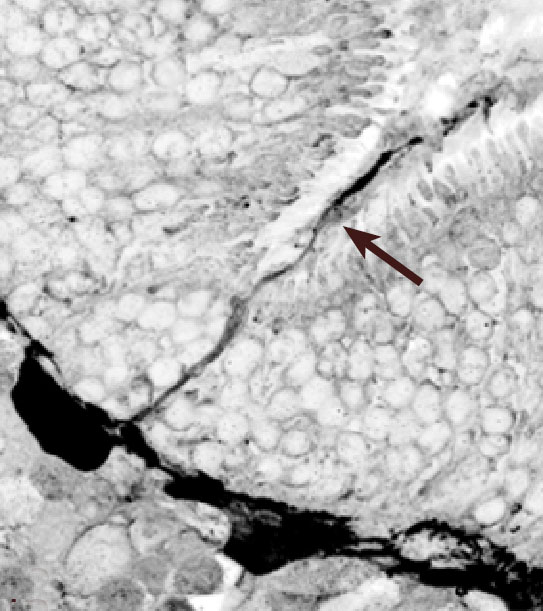

Figure 12. Confocal micrograph of a α-calretinin-positive HC outgrowth

Confocal micrograph of an α-calretinin-positive HC outgrowth (arrow) that extends across a narrowed ONL at a retinal fold in a 28 day detached cat retina. This is one in a series of 21 optical sections harvested at 0.3 μm intervals that are compiled as an AVI movie loop. Both the digitally inverted image and the AVI file were created using Image Pro Plus software.